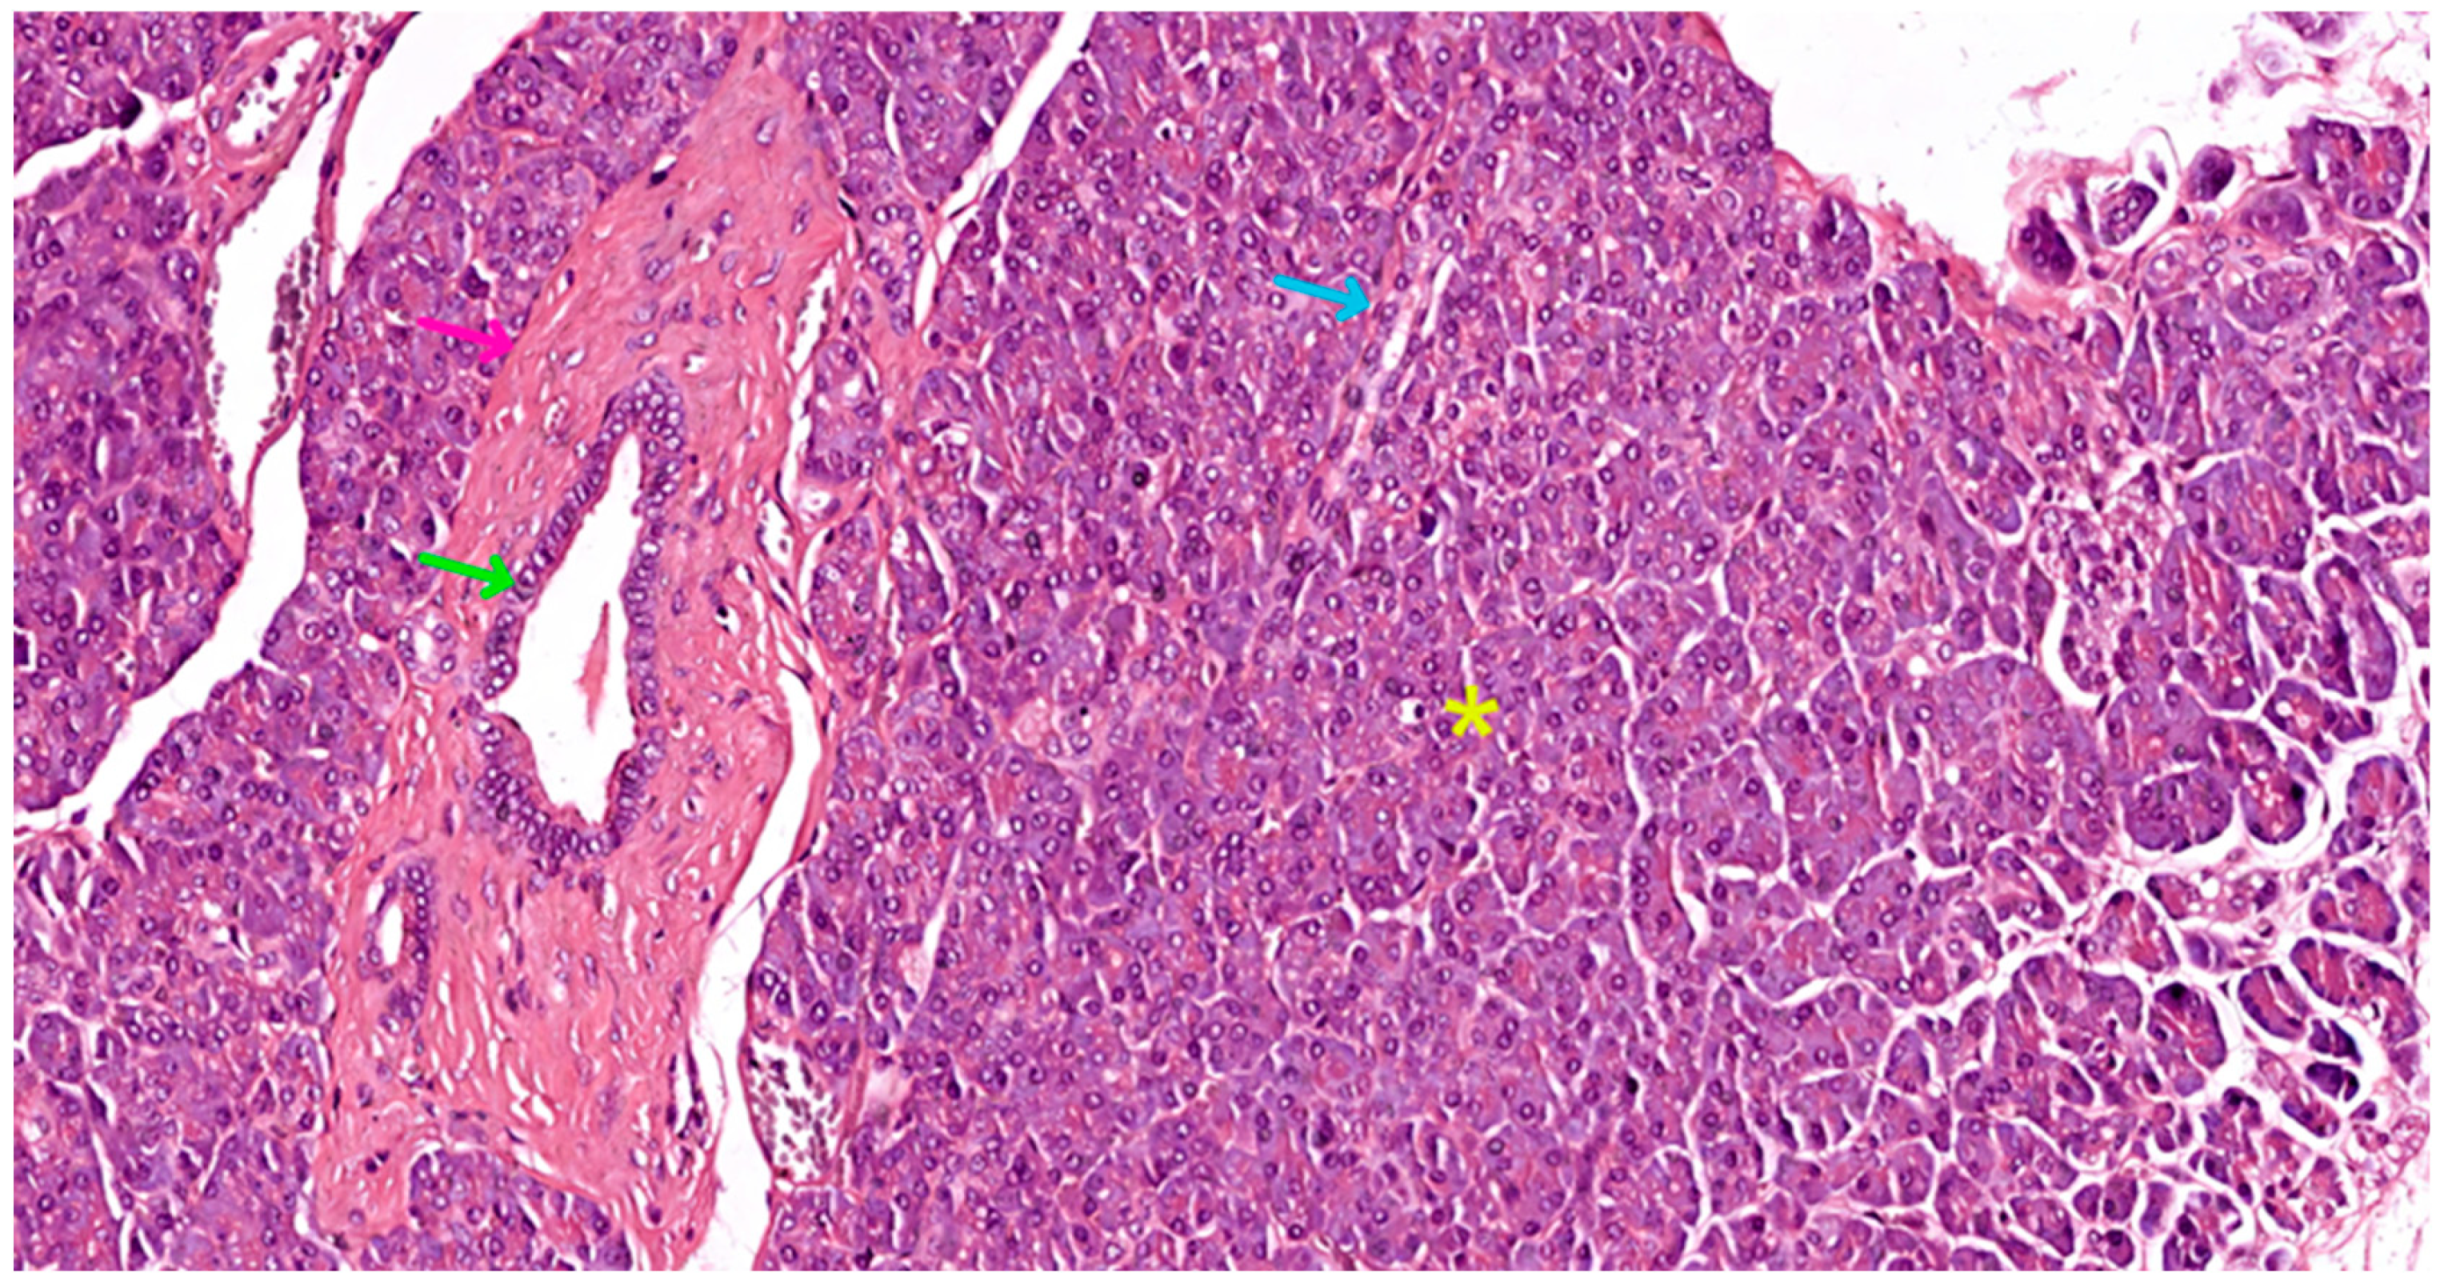

- Intralobular ducts—represented by intercalated ducts that continue the lumen of the acini and are delimited by simple cuboidal epithelium; intercalated ducts fuse to form proper intralobular ducts, which are larger and delimited by simple cuboidal or columnar epithelium; around these ducts, a loose connective stroma can be observed, with numerous reticulin fibers, yet quantitatively reduced overall; unlike major salivary glands, the exocrine pancreas does not have striated ducts (see Figure 4a,b).

- Interlobular ducts—located in connective trabeculae; they have a wide lumen and are delimited by simple columnar epithelium; they are surrounded by well-represented, dense, irregular connective tissue, which contains fibroblasts and myofibroblasts (see Figure 5).